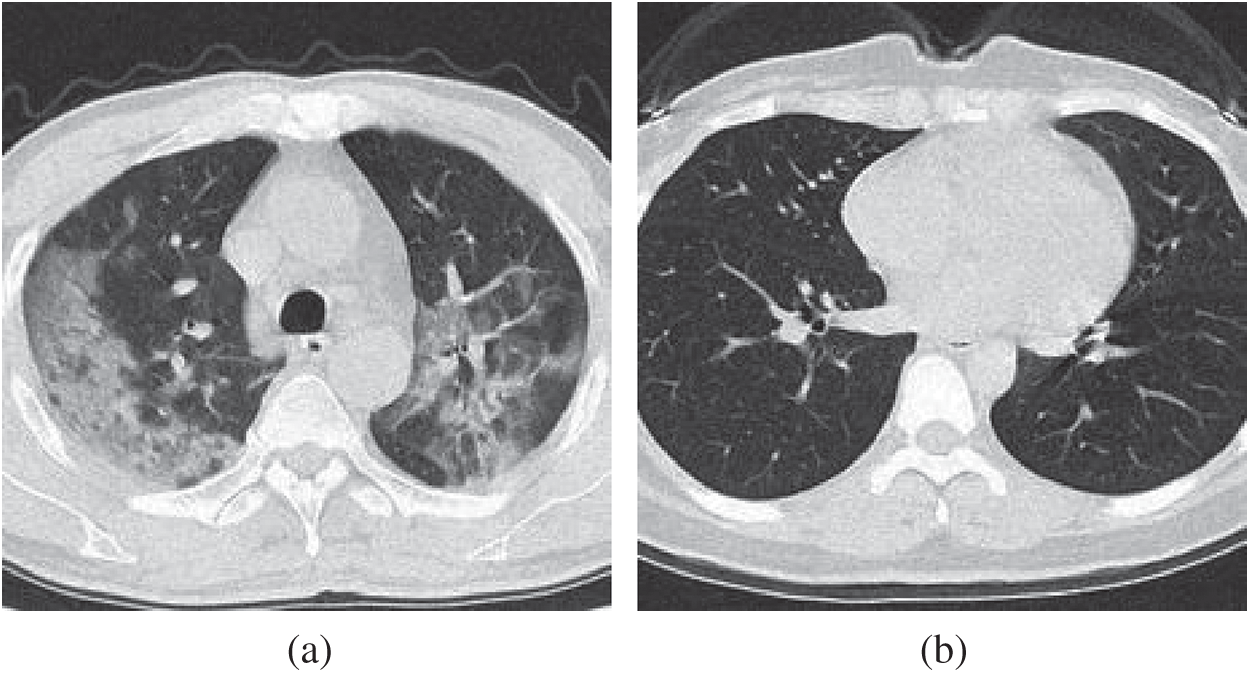

We use the dataset in reference [20], which contains 148 COVID-19 patients and 148 healthy control (HC) subjects. Slice level selection [20] was employed to generate

Figure 2: Example of preprocessed images (a) COVID-19 (b) HC